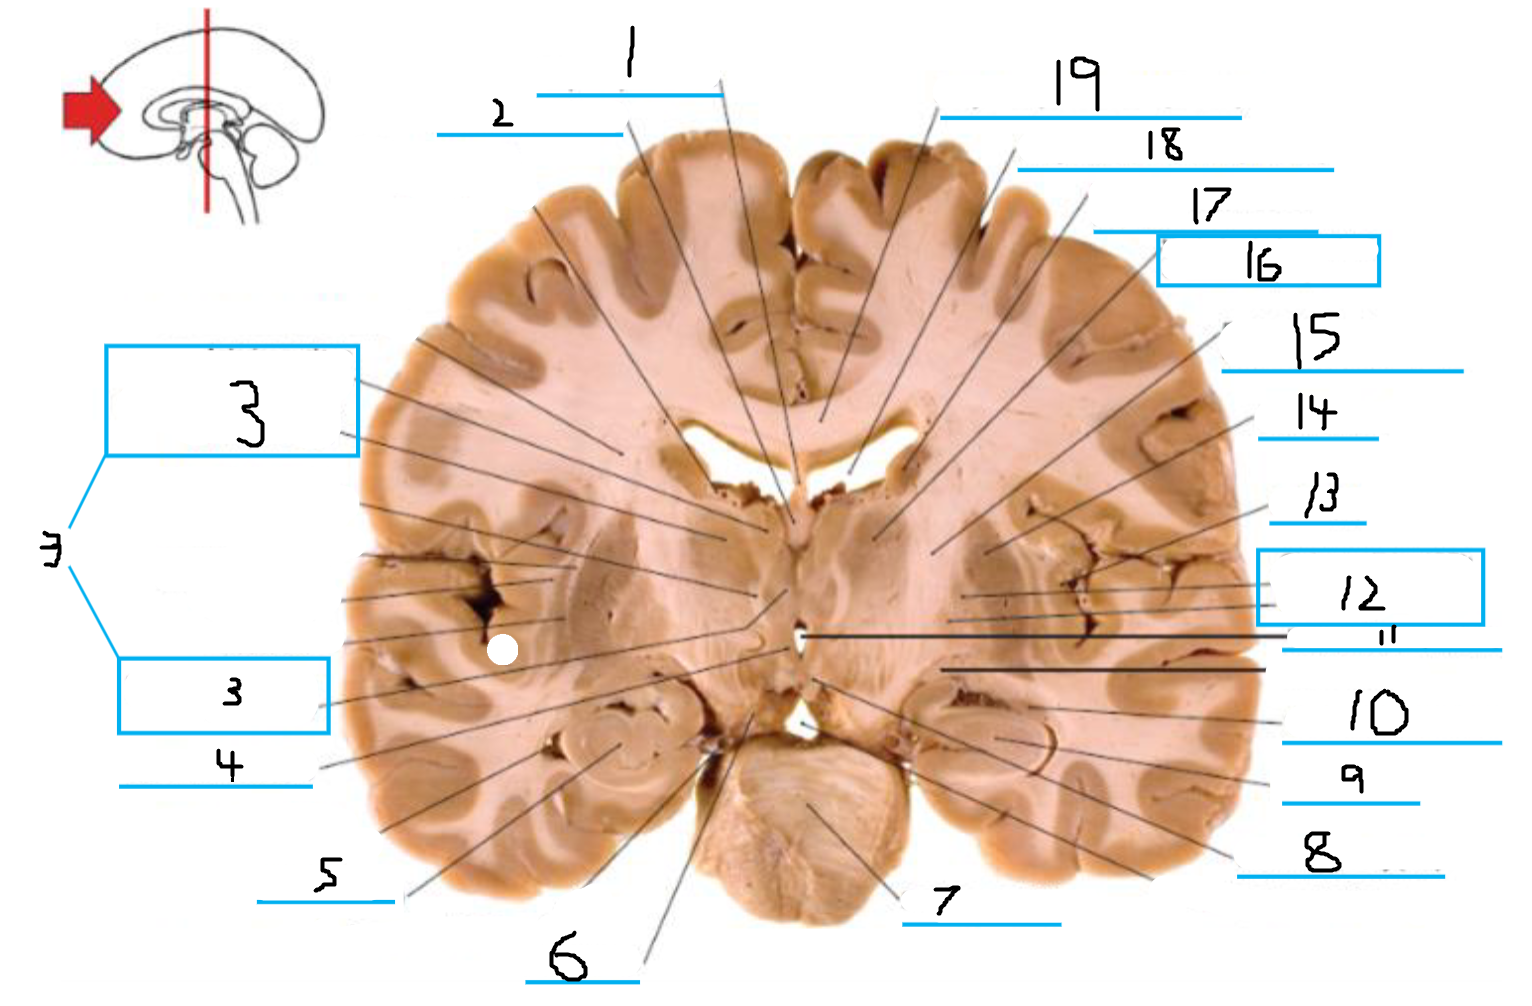

#1 is the:

Cingulate Gyrus

#2 is the:

Septum Pellucidum

#3 is the:

Lateral Ventricle

#4, #7, and #12 is the:

Fornix

#5 is the:

Third Ventricle

#6 is the:

Anterior Commissure

#8 and #11 is the:

Amygdala

#9 is the:

Hypothalamus

#10 is the:

Mammillary Body

#13 is the:

Insula

#14 is the:

Globus Pallidus

#15 is the:

Putamen

#16 is the:

Internal Capsule

#17 is the:

Caudate

#18 is the:

Corpus Callosum

#3 and #16 are the:

Thalamus

#4 is the:

#5 and #9 is the:

Hippocampus

Crus Cerebri

#7 is the:

Basilar Pons

#8 is the:

#11 is the:

#12 is the:

#14 is the

#19 is the: